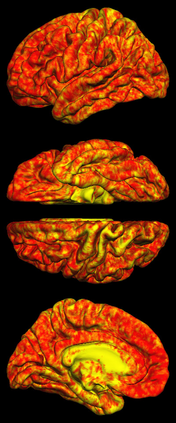

Due to various physical degradation factors and limited counts received, PET image quality needs further improvements. The denoising diffusion probabilistic models (DDPM) are distribution learning-based models, which try to transform a normal distribution into a specific data distribution based on iterative refinements. In this work, we proposed and evaluated different DDPM-based methods for PET image denoising. Under the DDPM framework, one way to perform PET image denoising is to provide the PET image and/or the prior image as the network input. Another way is to supply the prior image as the input with the PET image included in the refinement steps, which can fit for scenarios of different noise levels. 120 18F-FDG datasets and 140 18F-MK-6240 datasets were utilized to evaluate the proposed DDPM-based methods. Quantification show that the DDPM-based frameworks with PET information included can generate better results than the nonlocal mean and Unet-based denoising methods. Adding additional MR prior in the model can help achieve better performance and further reduce the uncertainty during image denoising. Solely relying on MR prior while ignoring the PET information can result in large bias. Regional and surface quantification shows that employing MR prior as the network input while embedding PET image as a data-consistency constraint during inference can achieve the best performance. In summary, DDPM-based PET image denoising is a flexible framework, which can efficiently utilize prior information and achieve better performance than the nonlocal mean and Unet-based denoising methods.